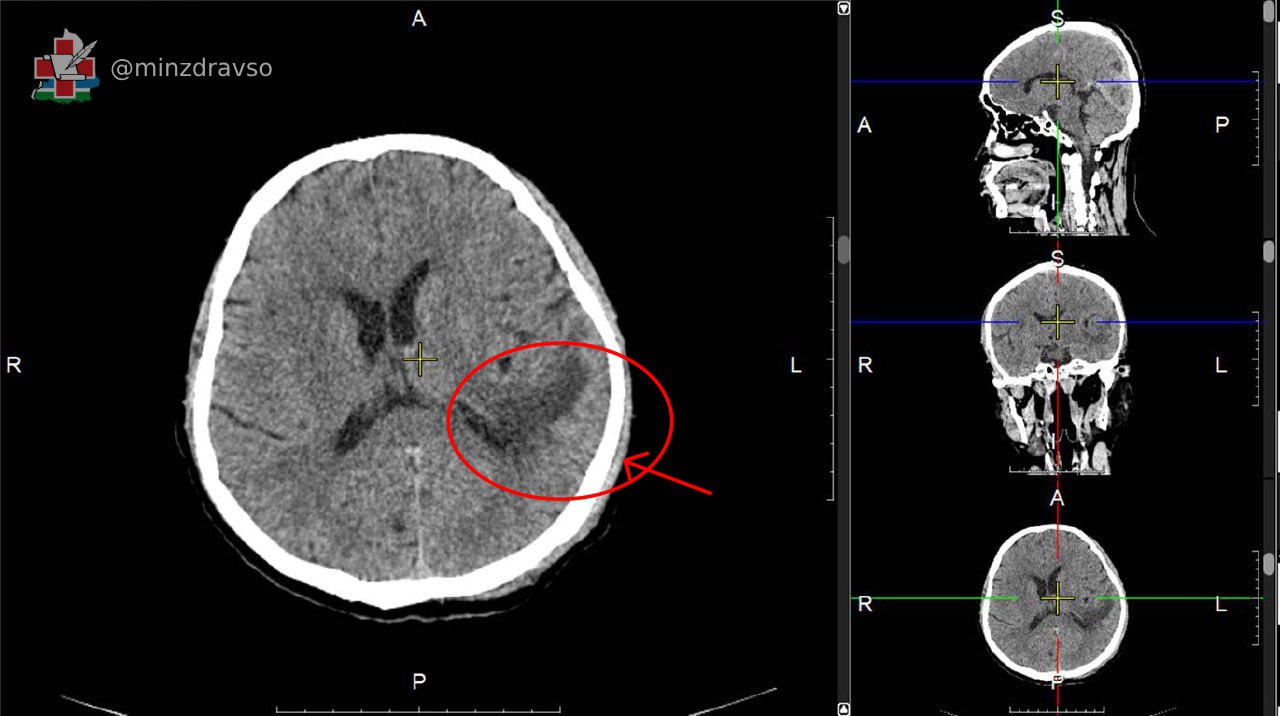

Совместная работа специалистов трёх медучреждений Свердловской области позволила спасти жизнь 51-летнему гражданину Китая, пострадавшему от геморрагического инсульта. У пациента была диагностирована внутричерепная гематома, требующая хирургического вмешательства. Наличие современного оборудования и развитие региональной сети первичных сосудистых центров благодаря национальным проектам «Здравоохранение» и «Продолжительная и активная жизнь», а также внедрение телемедицинских консультаций обеспечили быструю диагностику и успех операции.

Врачи связались с коллегами из Городской клинической больницы №40 Екатеринбурга для постановки точного диагноза и выбора тактики лечения. Мужчине провели компьютерную томографию, КТ-ангиографию сосудов головного мозга, и специалисты приняли решение выполнить хирургическое вмешательство. Пациента безотлагательно доставили в Городскую больницу №1 Нижнего Тагила, где нейрохирурги удалили внутричерепное патологическое образование, полностью восстановив кровоснабжение.